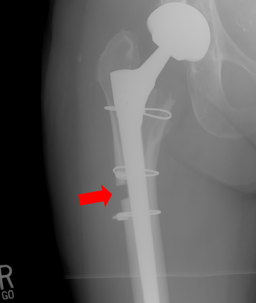

X-ray showing Mary Shea's femur after Dr. Copithorne's negligent operation

The case arose out of Dr. Copithorne’s failure to look at any of the X-rays he ordered for Mary at a post-operative appointment in March 2019, causing a 2-month delay in diagnosing the subsidence of her hip replacement. As a result, Mary required a much more invasive corrective surgery to fix the subsidence. Dr. Copithorne then attempted to perform the complex corrective surgery himself, and ended up leaving a large and unstable gap in Mary’s femur that subsequently required additional corrective operations at Maine Medical Center. Mary went through extensive physical therapy to try to restore full function in her right hip, but she was left with residual pain and weakness that kept her from fully resuming the active lifestyle she had hoped to get back to by having her hip replaced.